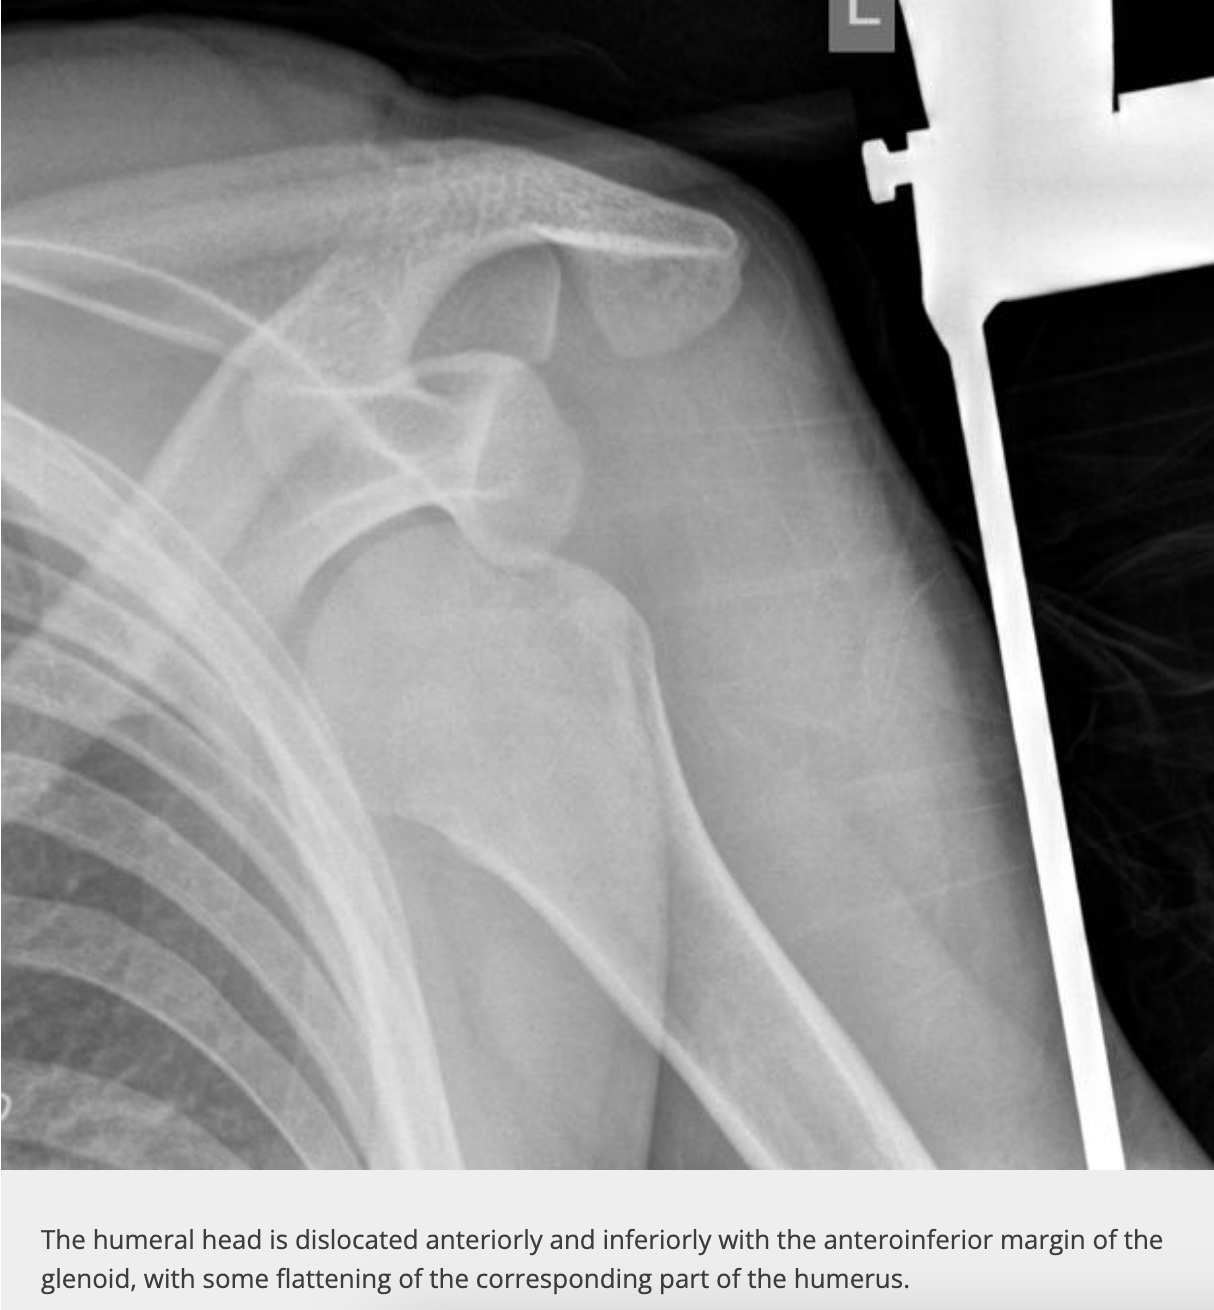

hill sachs defect

- anatomy: depressed fracture of humeral head

bankhart lesion

- anatomy: anterioinferior aspect of glenoid (or labrum?)

- contributes to anterior instability

- usually comes in a set with Hill-Sachs defect